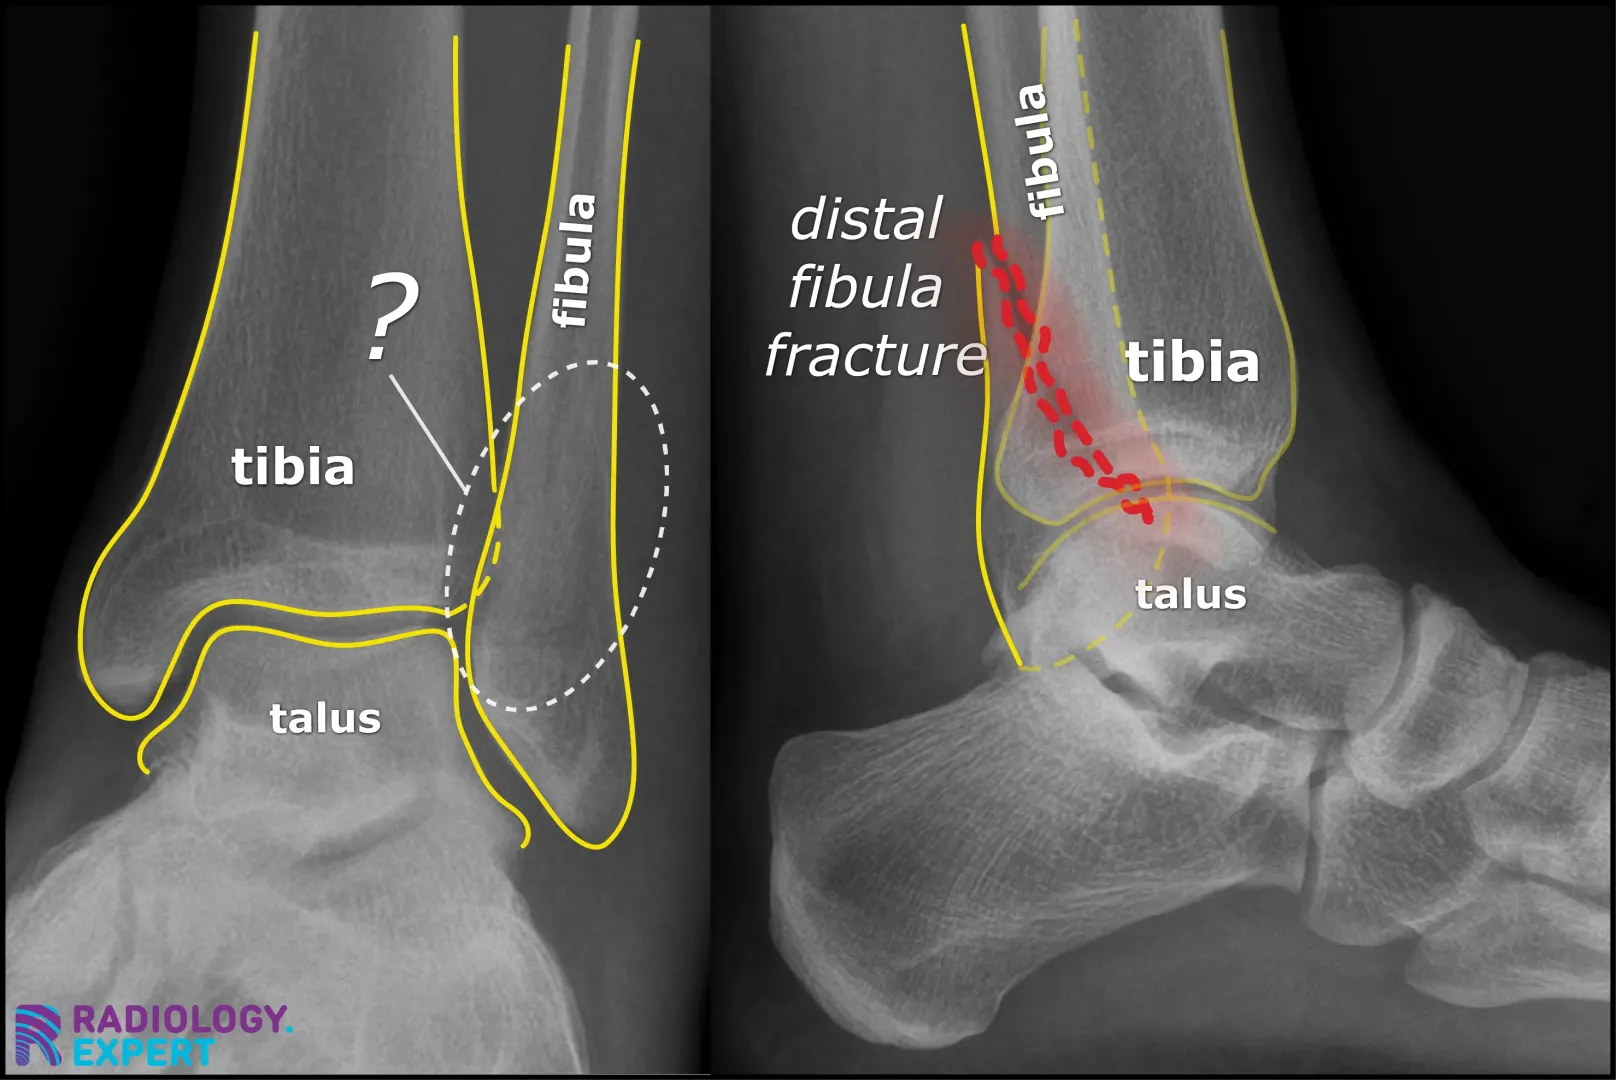

The principle is based on absorption of X-rays by bone (see also X-ray/CT Technique module), which ultimately results in a two-dimensional image. The risk with two-dimensional images is that a fracture line may be invisible if it runs parallel to the direction of the X-ray beam (Fig. 13). Standard protocols therefore include (at least) two projections: often an anteroposterior (AP) view and a lateral view. Depending on the anatomical location, additional projections may be obtained, such as an oblique view for hand or foot fractures, or specific views (e.g., mortise view for ankle fractures). The clinical suspicion and the anatomy of the region of interest determine the choice of projections.

Figure 13. Standard protocols generally include (at least) two projections. Ankle X-ray: the distal fibula fracture is almost invisible on the AP view (left) but clearly visible on the lateral view (right).

Click image to see overlay